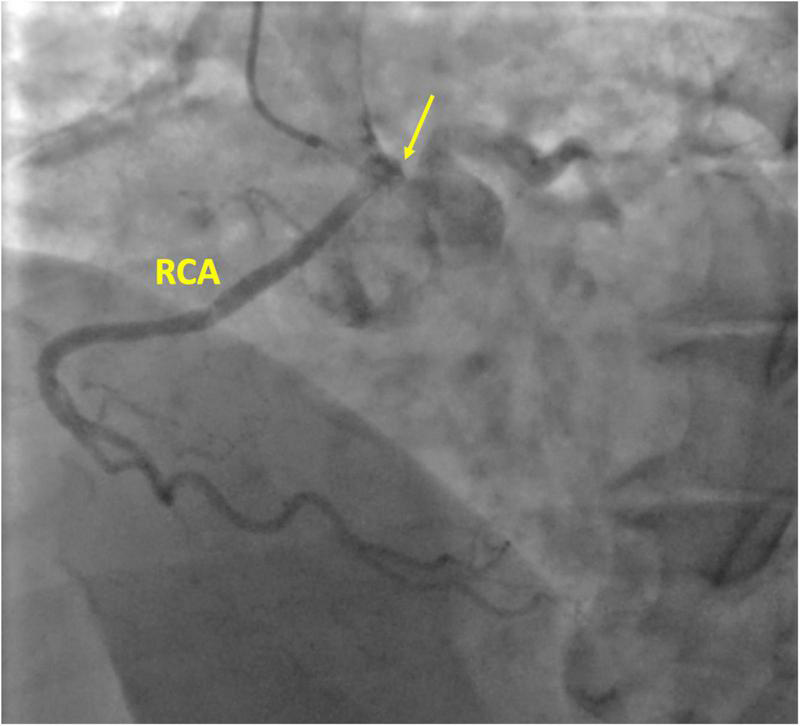

FIGURE 1

Coronary angiography of the right coronary artery (RCA). The yellow arrow is pointing the right coronary ostium originating from the left coronary sinus.

A 59-year-old white woman presented with chest pain and dyspnoea while sitting and watching a dramatic movie on TV. She had no preceding symptoms, and her past medical history was unremarkable. After admission to the emergency department, the symptoms resolved spontaneously. The myocardial necrosis markers (Troponin I and CK-MB) were not suggestive of myocardial infarction. The ECG revealed a normal sinus rhythm with no ischemic changes. She was transferred to the ward. Physical examination showed normal vital signs, regular heart rate and rhythm, and no extra sounds or murmurs. Transthoracic echocardiogram (TTE) showed preserved left ventricle ejection fraction (LVEF), normal wall motion, and no valvular diseases. The patient had a new onset chest pain while at rest. ECG showed new onset ST depression and T wave inversion in II, III, aVF, and V1-V3. She was quickly treated with sublingual nitroglycerine, and symptoms and ECG changes resolved. Repeat serial troponins resulted negative. She was scheduled for urgent cardiac catheterization with the diagnostic suspect of Prinzmetal angina. Coronary angiography showed unobstructed coronary arteries. After an acetylcholine test, coronary spasms were ruled out. Surprisingly, an R-ACAOS was also found (Figure 1). A CT coronary angiogram confirmed the origin of the right coronary artery (RCA) from the left sinus of Valsalva, with an intramural course and a malignant path between the aorta and the pulmonary artery (Figure 2). Despite being frightened, the patient consented to surgical correction of the coronary anomaly, which was performed by coronary artery bypass grafting. After a full sternotomy approach, the right internal mammary artery (RIMA) was harvested. Before cutting it distally, the TTFM was used to measure the RIMA flow, which was 22 mL/min. After dissecting the vessel distally, we noticed a nice flow with no sign of RIMA spasm. The RCA was isolated at its mid tract, and an off-pump coronary artery bypass grafting (OPCAB) has been performed with RIMA using a coronary shunt of 1.75 mm. After completing the anastomosis, transit time flowmetry (TTFM) showed a poor graft flow (6 mL/min with a pulsatility index (PI) of 2.0), indicating a competitive flow with the native RCA (Figure 3). Therefore, the RCA was proximally isolated and temporary occluded for 10 min in order to evaluate the best graft flow without ischemic drawbacks. At a graft flow of 20 mL/min with a PI of 0.7, the RCA was proximally ligated (Figure 3). The patient recovered uneventfully and was discharged 5 days after the operation. The patient was relieved that everything went nicely. One year after surgery, the follow-up evaluation of the patient confirmed the continuous absence of chest pain, dyspnoea, and a negative functional test with exercise stress echocardiography.